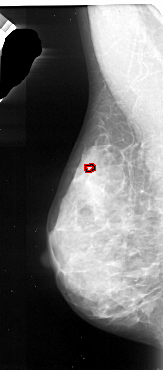

A_1092_1.LEFT_MLO

FILE: A_1092_1.LEFT_MLO.OVERLAY

TOTAL_ABNORMALITIES 1

ABNORMALITY 1

LESION_TYPE CALCIFICATION TYPE PUNCTATE DISTRIBUTION CLUSTERED

ASSESSMENT 4

SUBTLETY 1

PATHOLOGY MALIGNANT